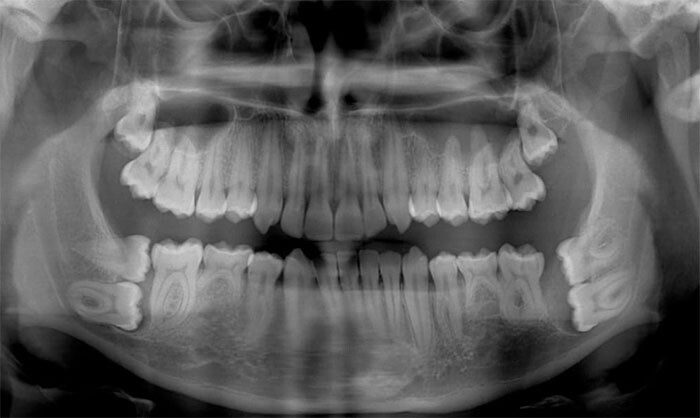

«Вчера у дантиста делал панорамный снимок зубов. Забыл снять очки»